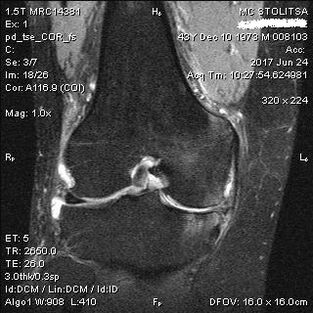

Arthrosis of the knee joint is diagnosed in the office of a rheumatologist or orthopedist.The doctor examines the damaged joint, palpates it, listens to complaints and asks additional questions.Conducts several tests - for example, asks the patient to bend the leg or take a few steps.Then, if it is necessary to clarify the stage of the disease or the nature of pathological changes, he will refer you to additional studies.For example, for computed tomography or radiography.